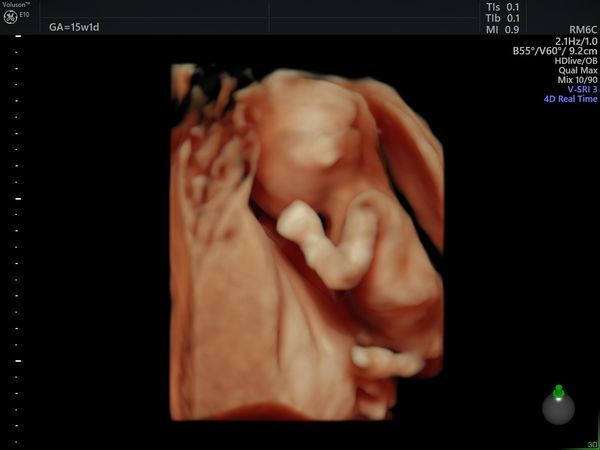

После скрининга пациентка пришла на УЗИ в 15 недель и 1 день. По УЗИ определялся один плод мужского пола, размеры плода пропорциональные, соответствовали менструальному сроку. Вес — 121 г (52 процентиль — норма). Пороков развития на момент исследования не было выявлено.

Плацента была расположена высоко от области внутреннего зева, структура не изменена. Количество околоплодных вод в норме. Длина шейки матки 35 мм (норма).